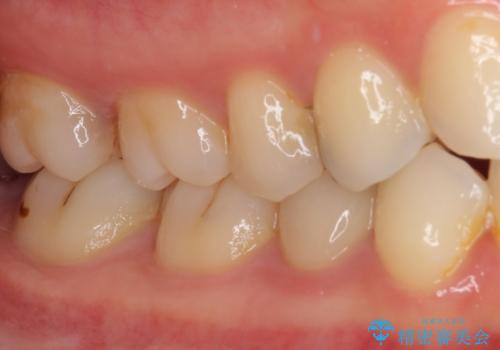

- 神経を抜く処置の後に装着したプラスチックのクラウンが外れてしまったとのことで来院された患者様です。

患者様自身、神経の取り除かれた歯はしっかりと製作されたクラウンを装着するべきと理解していただいていたため、オールセラミッククラウンにて補綴治療することとしました。

丈夫なクラウンを装着できただけでなく、形態や色調も自然に仕上げることができました。